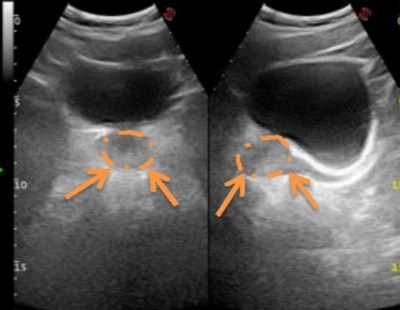

- Cálculos prostáticos, la cual es frecuente en pacientes con agrandamiento prostpatico, nosotros los diagnosticamos en menos del 20%.

- Quistes de retención, que aunque raros y sin significación patológica, preocupan a los pacientes

- Nódulos, en mas del 20 de cada 100 de pacientes, la literatura es contundente al respecto, solo un 20% de los nódulos detectados por ecografía corresponden a cáncer de próstata. El hecho de tener nódulos en la ecografía no es razón suficiente para realizar una biopsia de próstata.